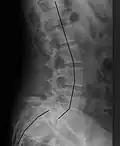

![]() | |

| X-ray of the lateral lumbar spine with a grade III anterolisthesis at the L5-S1 level | |

Spondylolisthesis refers to a condition in which one spinal vertebra slips out of place compared to another.[1] While some medical dictionaries define spondylolisthesis specifically as the forward or anterior displacement of a vertebra over the vertebra inferior to it (or the sacrum),[2][3] it is often defined in medical textbooks as displacement in any direction.[4][5]

Spondylolisthesis is graded based upon the degree of slippage of one vertebral body relative to the subsequent adjacent vertebral body.[6] Spondylolisthesis is classified as one of the six major etiologies: degenerative, traumatic, dysplastic, isthmic, pathologic, or post-surgical.[7] Spondylolisthesis most commonly occurs in the lumbar spine, primarily at the L5-S1 level, with the L5 vertebral body anteriorly translating over the S1 vertebral body.[7]